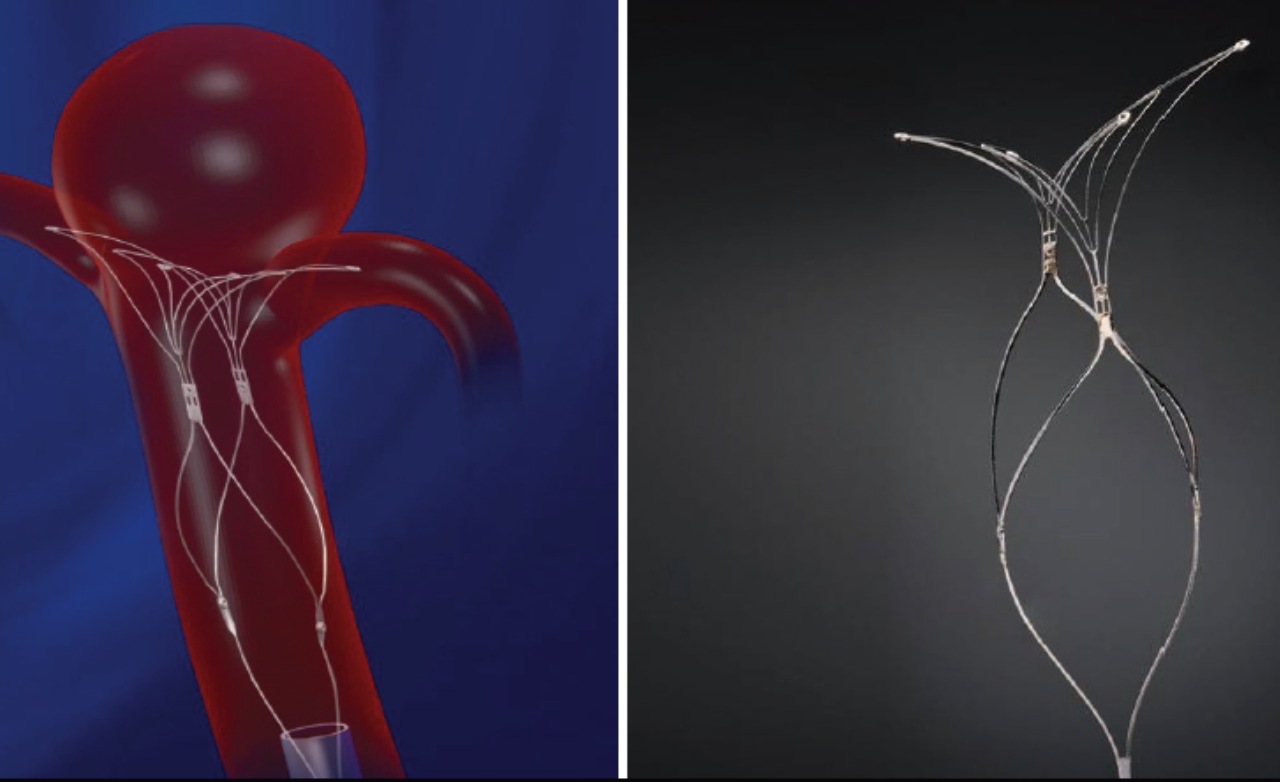

Intrasaccular devices are placed directly inside the aneurysm sac to block blood flow at its origin. They are useful for select wide-neck aneurysms.

These devices seal the aneurysm internally without affecting the parent artery or surrounding brain circulation.

Placed directly inside the aneurysm sac, these devices offer targeted treatment with minimal vessel manipulation for improved safety.